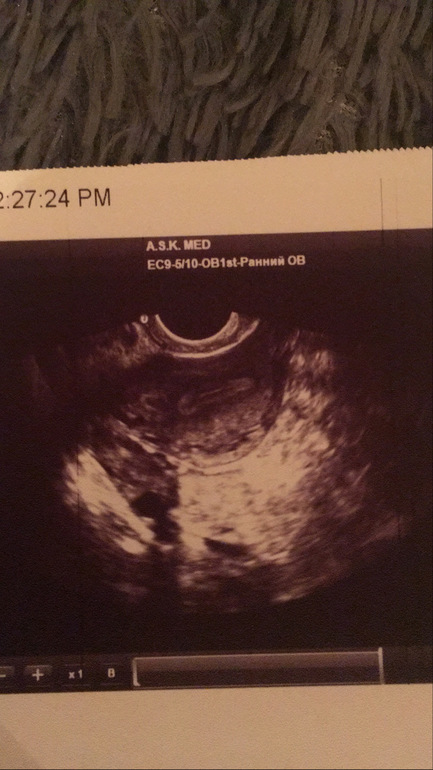

Точка в матке Возможна ли беременость если тест отрицательный?

Добрый день. Задержка 12 дней, цикл нерегулярный кормлю грудью. Планируем вторую беременость . 2 марта была на УЗИ в матке нашли точку, при этом желтого тела не нашли. Свободная жидкость в позадиматочном пространстве не определяется. Эндометрия 1,7 см повышенной эхогенности. в правом яичнике есть филикул до 18мм.

образование гипоэхогенное может быть чем угодно от кисты до гематомы. вряд ли беременность, потому что "точка" (полость") внутри миометрия (судя по снимку, но информативнее, разумеется, в динамике). сдайте хгч

Тоже точка в матке , беременность ли? Фолликулы в обоих яичниках, доминирующий в левом.